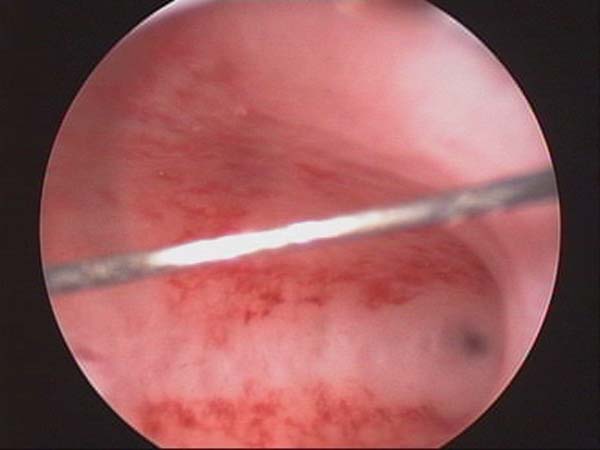

- Hysteroscopy Video clips

- Hysteroscopy Photos

Hysteroscopy Pictures | Dr N Layyous